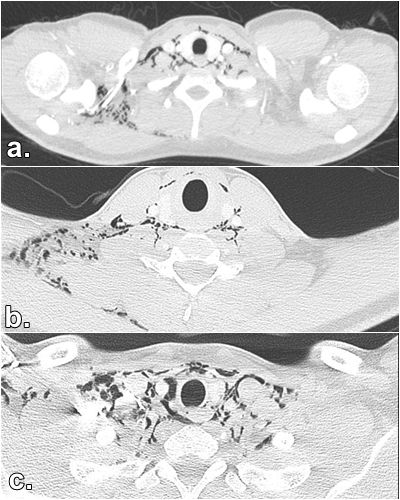

Se trata de un adulto joven de 20 años, sin antecedentes clínicos de importancia. Ingresa al servicio de urgencias consultando por cuadro clínico de 3 días de evolución consistente en dolor de cuello que se irradia al tórax con sensación pleurítica, refiere que el cuadro clínico ignición posterior a la ingesta de una tableta de azitromicina con un líquido espeso. Además, refiere que con el uso del vapeador aumentó inicialmente la sintomatología y después le fue aliviando. Al examen físico ingresa con signos vitales dentro de parámetros normales se palpa enfisema subcutáneo en región supraclavicular derecha y en cuello anterior derecho, por lo que se realiza radiografía de tórax, la cual se reporta dentro de parámetros normales. Paraclínicos de extensión con hemograma el cual revela leve leucocitosis y neutrofilia, sin anemia, función renal conservada. Se indica la toma de tomografía de cuello y tórax contrastada con el fin de descartar lesión de la vía aérea. (Fig.1y2) La tomografía describe enfisema subcutáneo que compromete base del cráneo, cuello derecho, región supraclavicular, paravertebral y axilar derecha que diseca planos musculares sin evidenciarse claramente origen de la lesión. Por otra parte, la tomografía contrastada de tórax muestra un neumomediastino extenso, probablemente espontáneo, sin garantizar que no hay una perforación esofágica asociada. Se valora paciente en conjunto con servicio de Emergenciología, Neumología y Cirugía de tórax, por lo que se indica traslado a la Unidad de Cuidado Intensivo (UCI), con la finalidad de vigilar vía aérea del paciente y realizar exámenes afines que complementen el cuadro clínico del paciente; se indica entonces realización de esofagograma (Fig. 3), endoscopía de vías digestivas altas y fibrobroncoscopía.

Fig.1 Tomografía de cuello contrastada del paciente. a: Tomografía de cuello contrastada ventana pulmonar corte axial: en la cual se evidencia enfisema subcutáneo abundante en cuello disecando planos musculares. b:se observa enfisema subcutáneo en fosas supraclaviculares y base del cuello. c:Se observa enfisema subcutáneo disecando tejidos musculares con región axilar derecha